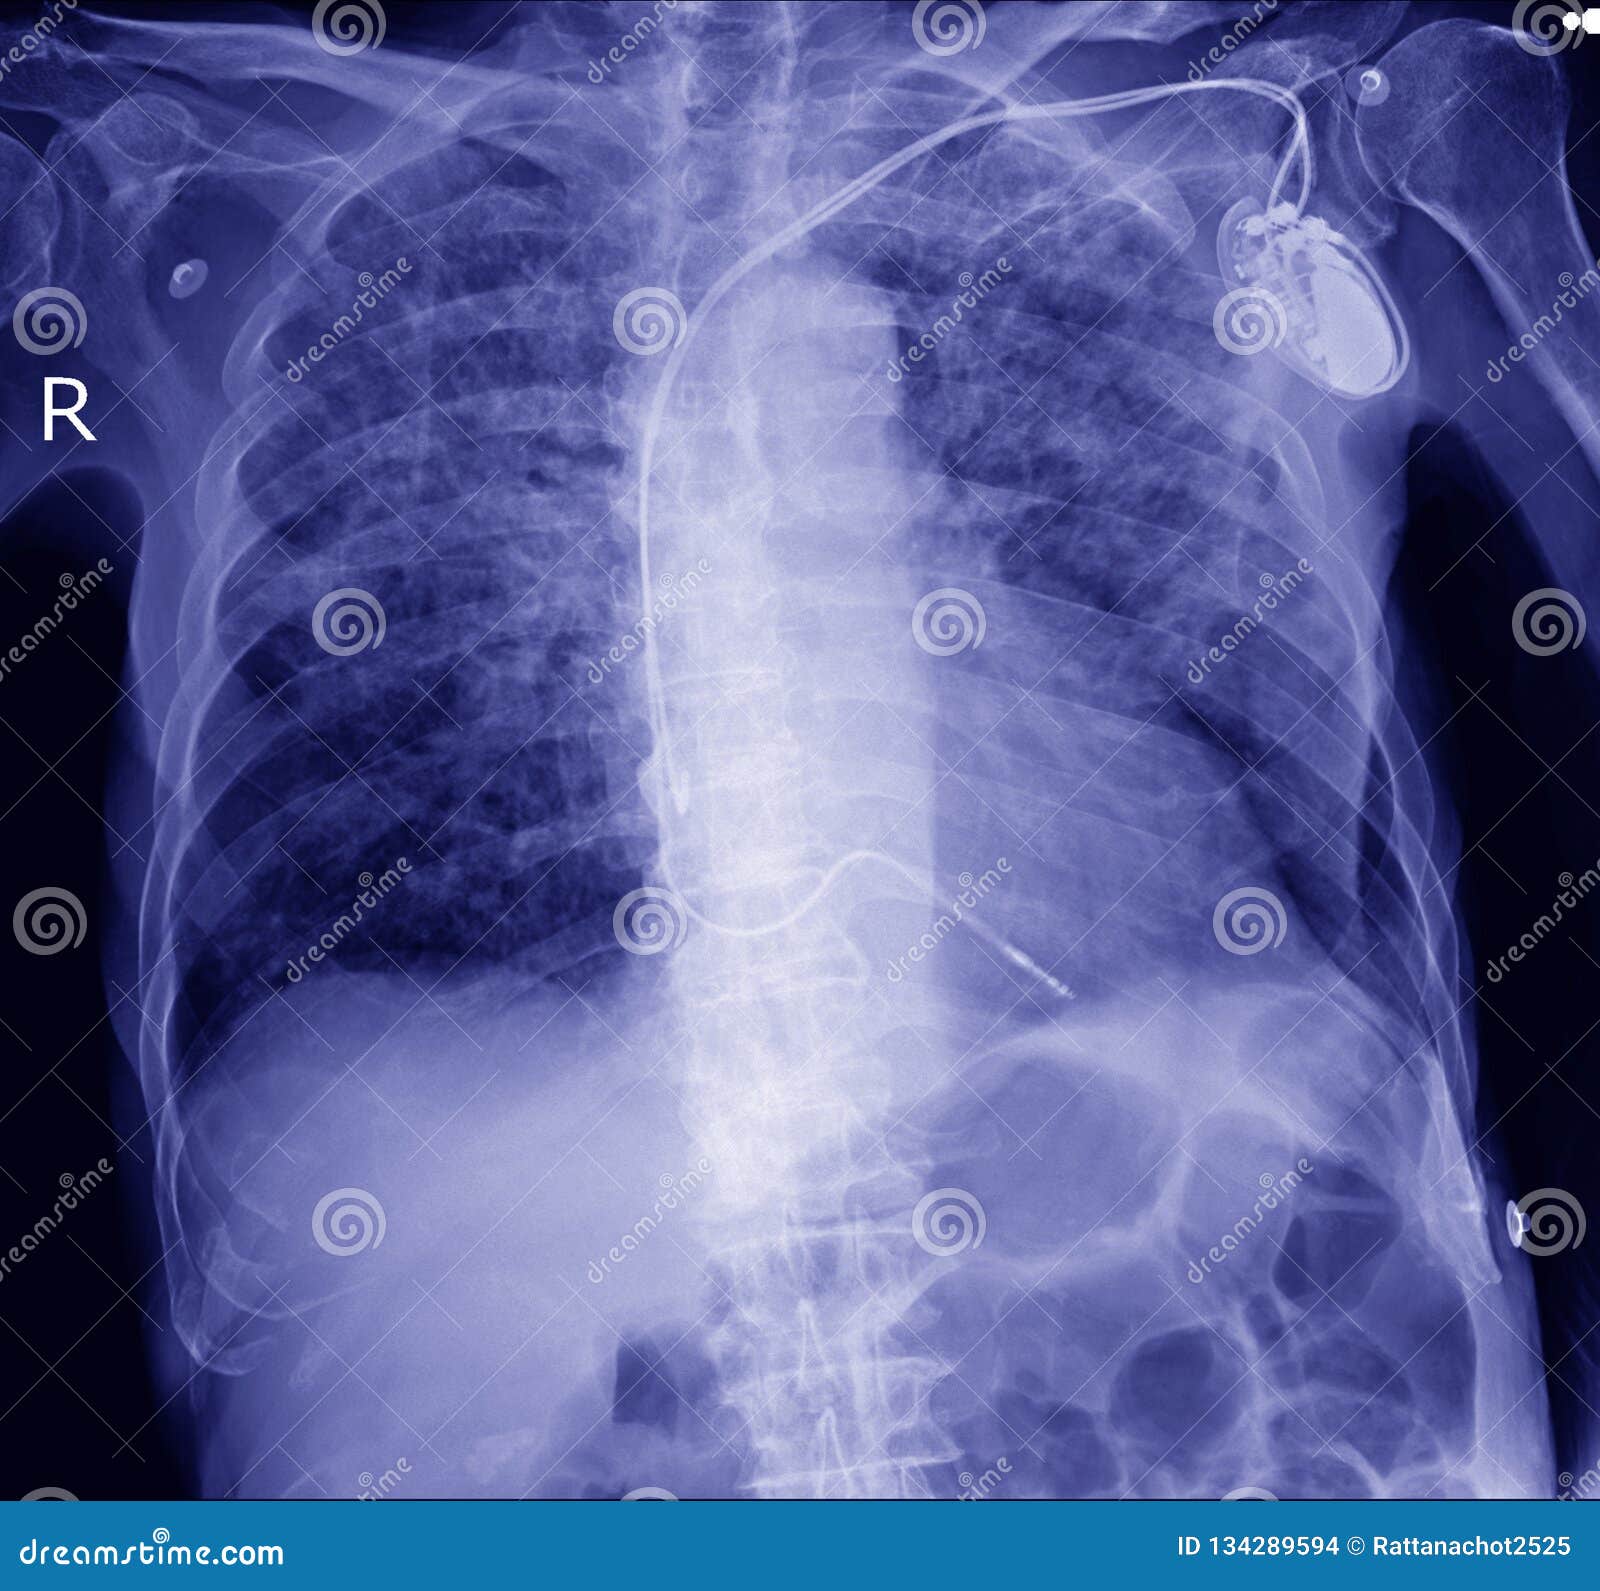

VVIR pacemaker in xray image in cardiac catheterization laboratory Cardiac Catheterization X Ray A cardiac catheter is a thin,. cardiac catheterization is a procedure used to show on a computer monitor diseases that affect the heart. shortening ft and cine acquisition times has direct and obvious effects on radiation exposure per. in cardiac catheterization (or cath), your healthcare provider puts a very small, flexible, hollow tube (catheter) into a blood. Cardiac Catheterization X Ray.

Pacemaker in Xray Image in Cardiac Catheterization Laboratory Stock Cardiac Catheterization X Ray shortening ft and cine acquisition times has direct and obvious effects on radiation exposure per. in cardiac catheterization (or cath), your healthcare provider puts a very small, flexible, hollow tube (catheter) into a blood vessel in the groin, arm,. cardiac catheterization is a procedure used to show on a computer monitor diseases that affect the heart. A. Cardiac Catheterization X Ray.